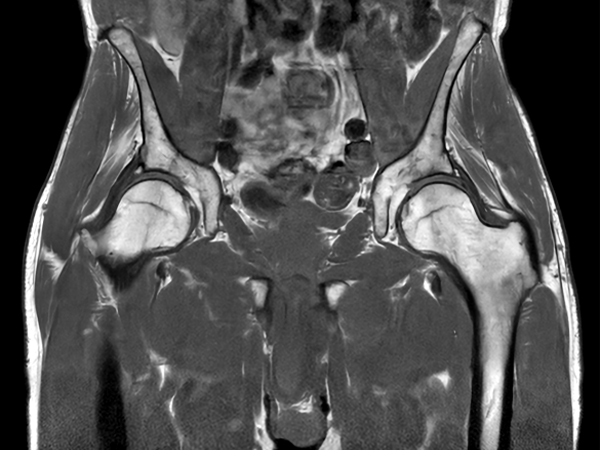

Fast bilateral hips, with SmartSpeed Precise

Used Solution